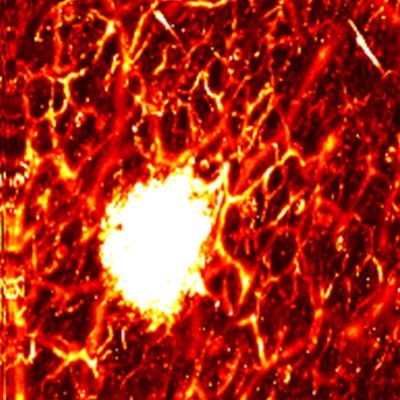

MAP

Cross sectional view

Surface(Depth) view